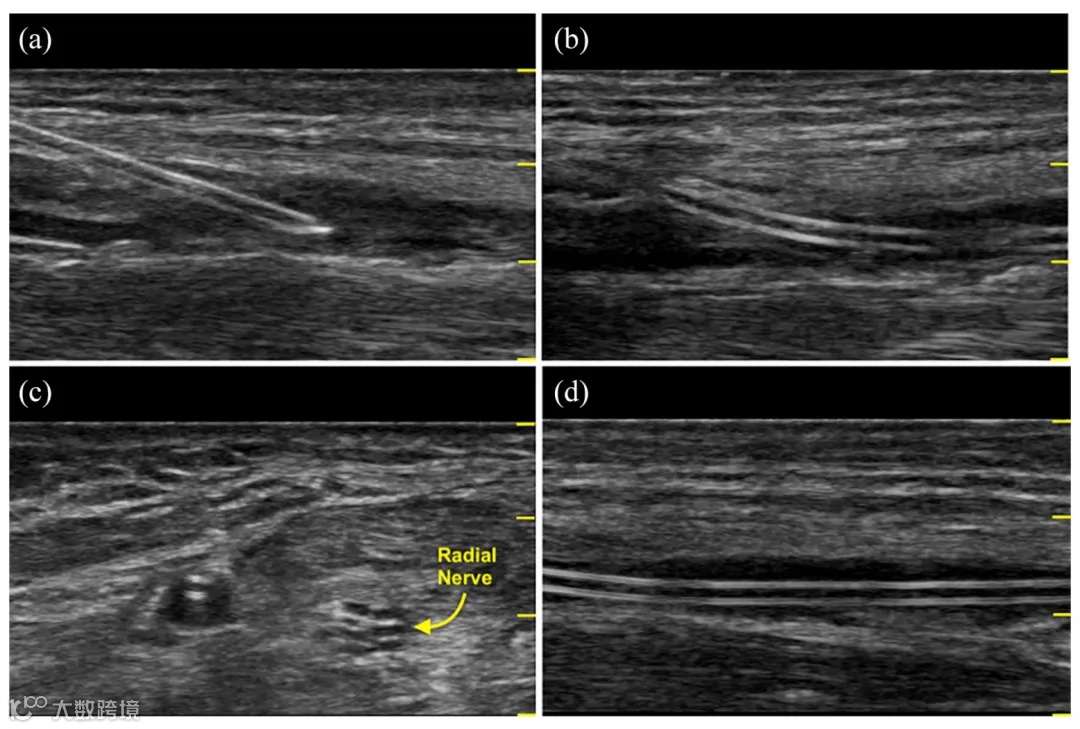

较低的插入角度 (<30°–45°) 可降低导管体扭结和相关设备故障的风险。平面内或平面外超声技术的选择将改变插入角度(和导管停留长度)(见图 1和2)。最近的出版物表明,在适当的插入角度和优化总导管在动脉中长度的情况下,三角学在 USG 血管通路过程中提供了好处。

图 1.超声视图显示 (a) 30°–45° 针头插入角度,(b) RAC 停留角度,(c) CVR 横向视图,以及 (d) CVR 纵向视图和 RAC 停留长度。CVR:导管与血管的比率;RAC:桡动脉导管。